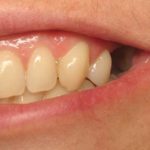

This patient had lost his front tooth due to an accident and had an Implant placed to replace it.